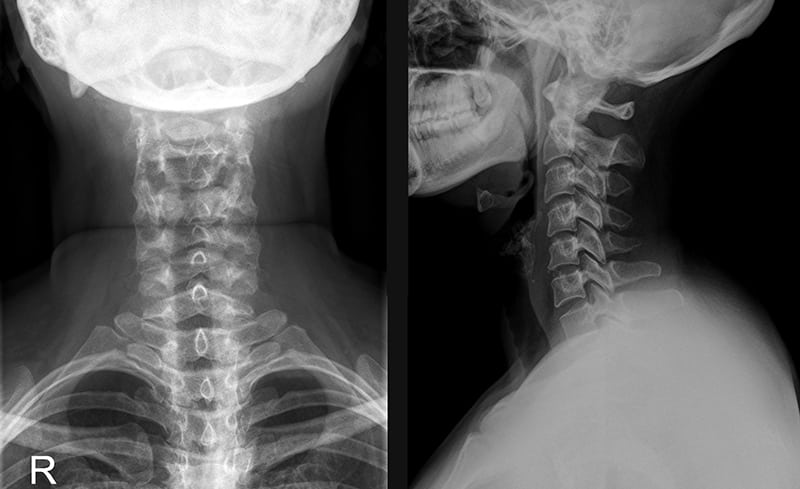

При диагностировании грыжи рентгенография неинформативна, так как выпячивание на полученных снимках не визуализируется. Но зато хорошо просматриваются признаки остеохондроза, которые и становятся основной причиной смещения ядра.

Выявить фораминальную грыжу можно с помощью МРТ или КТ. Инструментальные исследования позволяют установить локализацию выпячивания, его размер и форму, степень сужения позвоночного канала. Если у пациента есть противопоказания для проведения КТ или МРТ, то назначается миелография с контрастом.